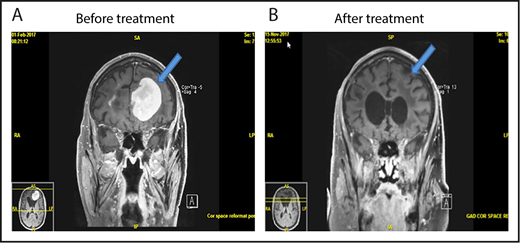

The ORR for all 25 eligible patients was 48% (12 of 25; 95% CI, 27.8%, 68.7%) with 6 CR, 2 CRu, and 4 PR (Figure 1). The ORR for the MTD dose level was 50% (8 of 16; 95% CI, 24.7%, 75.4%) with 5 CR, 1 CRu, and 2 PR. The ORR for the 23 PCNSL patients was 48% (11 of 23; 95% CI, 26.8%, 69.4%) with 6 CR, 2 CRu, and 3 PR. The 12 responders completed a median of 6.5 cycles (range, 2-42 cycles). Median DOR was 4.7 months (95% CI, 4.5-NE; range, 1.1-28.8 months). Median PFS was 5.3, 9, and 5.3 months for the whole study (Figure 1B), responders (Figure 1C) and PCNSL patients, respectively. The outcome events and total number of treatment cycles for each patient are summarized in a swimmer’s plot (Figure 2). Brain MRI of a PCNSL patient who achieved CR is shown in Figure 3. Two patients with PVRL were treated at the MTD dose level. One patient had disease progression after cycle 18. The other patient had PR after cycle 2 and remains on treatment after cycle 7.

MRI of brain showing CR of relapsed PCNSL to the study treatment. This patient with relapsed PCNSL (A) achieved CR after cycle 8 (B). He achieved PR after cycle 4. This case corresponds to patient 21 in Figure 2.